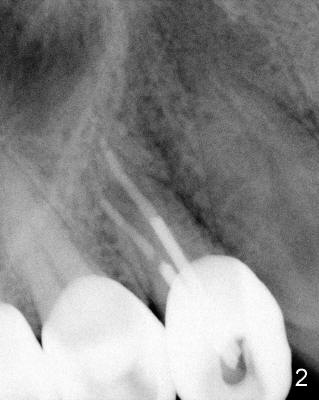

A 68-year-old male patient presented to office in March 2011 with chief complaint "upper right tooth is not comfortable". Clinical exam shows missing teeth: #13,14,30, and 31, replaced by removable partial dentures. The tooth #5 has mild mobility and percussion. Pocket depth is within normal limit. X-ray shows no significant finding (Fig.1,2). Three months later, he returned with chief complaint "The tooth has swelling". It appears that there is exostosis on buccal aspect of upper teeth. There is no erythema or tenderness on buccal mucosa around the tooth #5). But X-ray shows periradicular radiolucency (arrowheads in Fig.3,4). Cone Beam CT was recommended to confirm diagnosis of root fracture. Approximately one month later, abscess developed with fistula formation. Symptoms were controlled by taking Amoxicillin. On August 2, 2011, the patient returned for prophylaxis. The fistula was present (arrowhead in Fig.5). Gutta percha #30 was inserted into the fistula. PA was taken. The point of the gutta percha (blue arrowhead in Fig.6) points to enlarged periradicular radiolucency (black arrowheads). Deep pockets were in distobuccal and lingual. Decision was made to extract the tooth. Fig.7 shows the socket immediately extraction. The buccal plate is perforated. The septum (*) is not intact. Cracking sounds were heard during extraction. In fact the lingual root is obliquely fractured with exposed post (Fig.8: *). There is another cracking line from the buccal root to the lingual one (arrowhead). In brief, the earliest sign of root fracture is nonspecific. It should alert us to its suspicion.